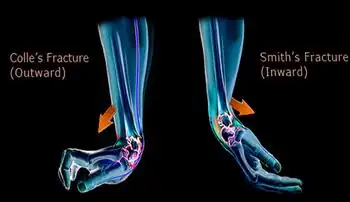

A Smith's fracture is a type of fracture of the forearm near the wrist in which the broken end of the radius is bent downwards.[1] The break is oblique, does not extend into the joint, and is associated with being pushed out of place.[2]

The distal fracture fragment is displaced volarly (ventrally), as opposed to a Colles' fracture which the fragment is displaced dorsally. Depending on the severity of the impact, there may be one or many fragments and it may or may not involve the articular surface of the wrist joint.